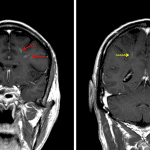

- Corresponding faint linear and nodular areas of enhancement in the bilateral frontal white matter and to a lesser extent in the bilateral parietal white matter

- Intermixed foci of susceptibility artifact

Intravascular lymphoma